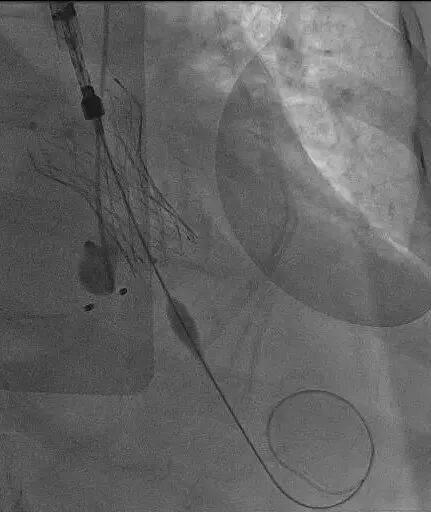

生死关头,在与患者家属充分沟通后,心血管诊疗中心一病区主任敖钦主任医师、主诊组长曹俊达副主任医师迅速集结心内、胸外、超声、麻醉、介入护理等多学科团队,并调动重症ECMO团队全程为手术保驾护航。团队选择经左侧颈总动脉入路,而这一术式,在急诊抢救、无术前CTA精准导航的双重极限条件下,无疑是一场超高难度的生死挑战。颈动脉是大脑供血命脉,操作稍有闪失即可引发灾难性卒中;无CTA就无法评估血管内斑块、走行异常、主动脉弓部情况,每一步都是“雷区”。心胸外科诊疗中心陈世雄副主任医师团队精准暴露左侧颈总动脉,穿刺、置管一气呵成。术中仅凭食道超声即时评估选择瓣膜型号,导丝“盲穿”穿过主动脉弓进入左心室。从穿刺到瓣膜释放,全程仅用时13分钟。造影显示瓣膜位置完美,无瓣周漏,冠脉通畅。术后患者血压即刻改善,次日心功能明显恢复,第五天转回普通病房,康复顺利。